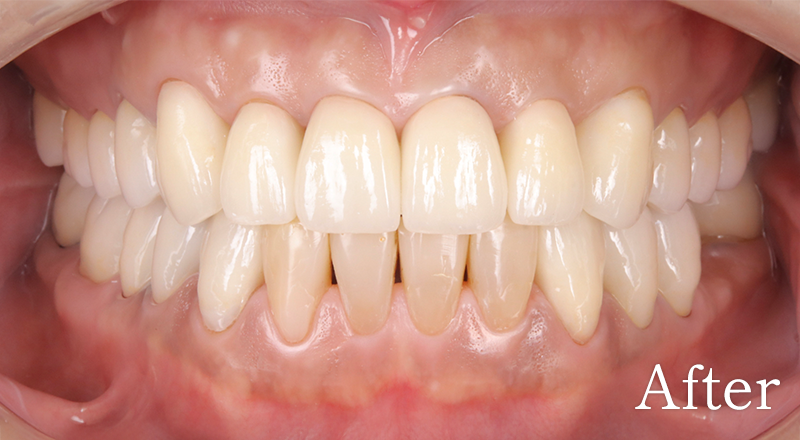

CASE4

骨格1級患者に対し、臼歯部にインプラント治療を行い咬合回復を行なった1症例

主訴 右側でうまく噛めない

治療内容 下顎臼歯部インプラント、咬合再構成、上顎矯正治療、セラミック治療

治療期間 約2年

費用 診断料:22万円(税込)

下顎顎臼歯部インプラント埋入手術:22万円(税込)×4本

セラミック補綴:22万円(税込)×4本

セラミック治療:11万円(税込)×9本

矯正治療:44万円(税込)